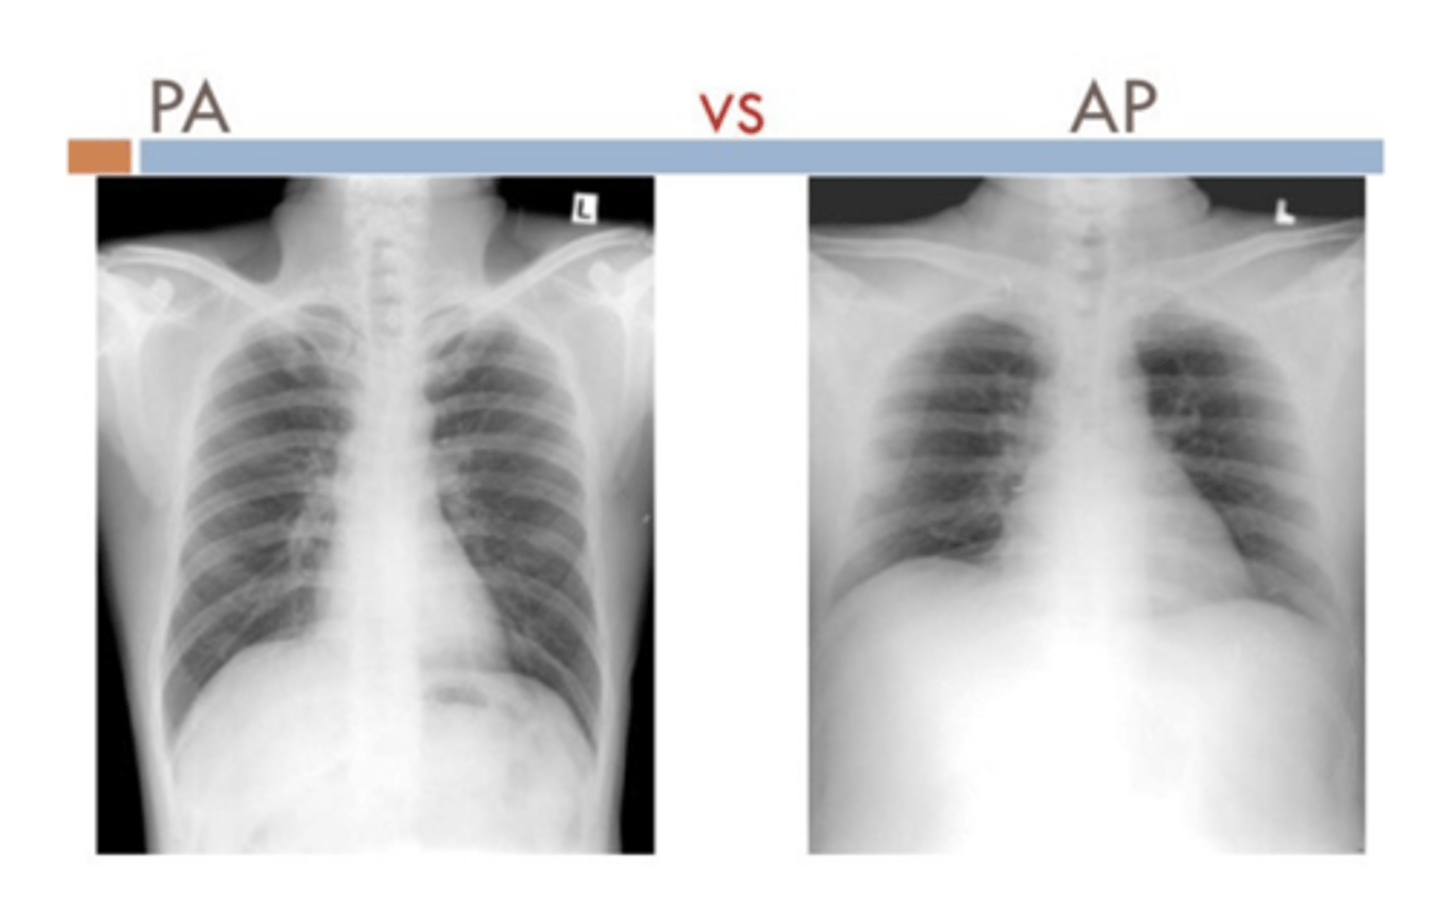

•2. What type of film? AP, PA, portable or lateral? Correct exposure?

•Routine CXRs include PA and lateral views with the patient in the upright position.

⚬AP and supine (portable) films make the heart appear enlarged and the lungs hypoinflated.

What structures are more visible PA vs AP?

PA

⚬Scapula in periphery

⚬Clavicles project over lung fields

⚬Posterior ribs are distinct

AP

⚬Scapula are over the lung field

⚬Clavicles above apex of lung

⚬Anterior ribs are distinct

<p>PA</p><p>⚬Scapula in periphery</p><p>⚬Clavicles project over lung fields</p><p>⚬Posterior ribs are distinct</p><p>AP</p><p>⚬Scapula are over the lung field</p><p>⚬Clavicles above apex of lung</p><p>⚬Anterior ribs are distinct</p>